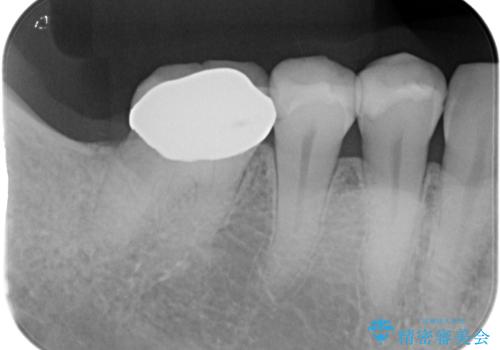

- 右下欠損部のインプラント治療を希望して来院された患者様です。

右下の欠損部を長期間欠損を放置していたことで、咬み合う上の奥歯が動いてしまっていたので、まずは上顎奥歯の部分矯正を行うこととしました。

理想的な咬み合わせに改善した上で、インプラント補綴治療を行うこととしました。